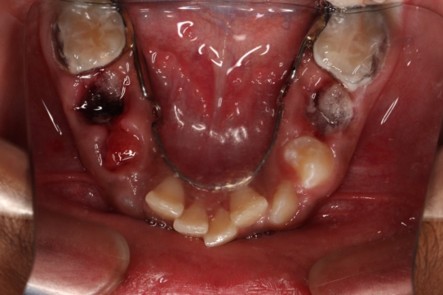

Tooth decay is a common issue seen in kids due to high sugar intake. Broken teeth from injuries, teeth alignment, finger sucking, bad breath are the most common dental problems in children. They can be prevented and cured as the teeth are young and are in growing phases.

- Pulpotomy, pulpectomy